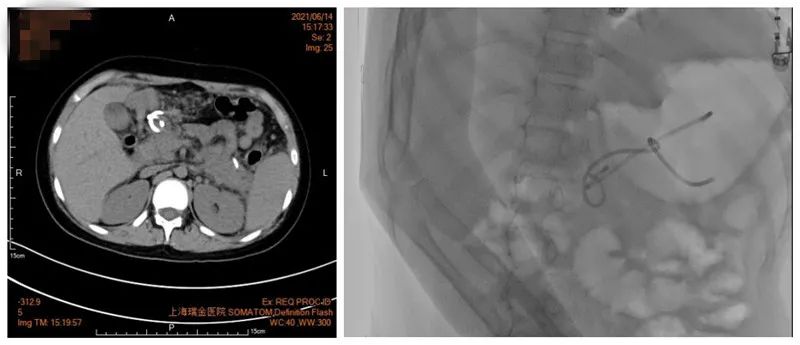

随着每天囊腔内液体的流出,小熙的腹胀和呕吐症状很快开始好转,并且逐渐开始从流质恢复到半流质饮食了,CT显示假性囊肿明显变小……看着女儿慢慢恢复活力,父母也有了笑容。

不过,鼻子里的引流管让小熙感觉不舒服,一直吵着要拔掉,考虑到囊肿基本消失,且孩子耐受性差,医生将鼻囊肿引流管剪断,改为引流支架来使用。

引流6天后囊肿消失(左图)

囊肿里剩余2根引流管(右图)